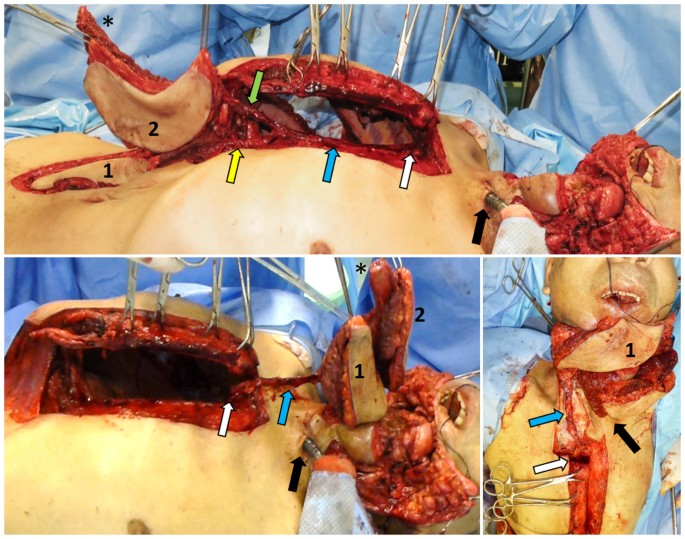

Prior to PIMOC dissection, we explored the neck vessels viability and confirmed a lack of vessel patency suitable for safe microsurgical tissue transfer. The PIMOC was then harvested as described in the cadaver study, with one exception. In the cadaveric dissections, the rib cartilage was included in the flap to create a versatile chimeric design in order to expand our reconstructive options. In the clinical setting, costal cartilages were not included in the flap because the mandible defects required bony reconstruction only. Costal cartilage was therefore preserved to prevent undue donor site morbidity. The 6th or 7th rib osteomyocutaneous component was selected based on vessel caliber and ease of pedicle dissection. The internal mammary pedicle was pivoted at the inverted L osteotomy, rotated around the first rib and clavicle, and positioned within the loose subcutaneous tissue at least 3 cm away from the tracheostomy (Fig. 2). Final inset with bone fixation and multi-layered closure was performed.

PIMOC surgical technique. (A) Exposure of the mediastinum through an inverted L sternotomy incision and dissection of the IMA pedicle (blue arrow). The VRAM (1) is supplied by the DSEA (yellow arrow). The osteomyocutaneous component (2) contains the 7th rib (*) in this case and is supplied by both the musculophrenic and intercostal arteries (green arrow). (B) Rotation of the PIMOC cephalad. The pivot point of the IMA pedicle is at the lower margin of the first rib (white arrow). (C) Flap inset. The IMA pedicle positioned within the loose subcutaneous tissue at least 3 cm from the tracheostomy site (black arrow). The rib osteomyocutaneous component was used for reconstruction of the mandible and oral lining, and the VRAM component was used for external coverage.

The PIMOC included a 6th rib segment in two patients and a 7th rib segment in two patients, three of which contained a myocutaneous component supplied by intercostal perforators. In four patients, we harvested the rectus abdominis muscle with overlying skin supplied by epigastric artery perforators, and, in two patients (patients 2 and 3), we included an SSEP cutaneous flap (Figs 4 and 5). In Video, Supplemental Digital Content 2, we demonstrate the dissection and clinical application of the PIMOC in salvage head and neck reconstruction cases.

PIMOCs. (A) Patient 1. Left extended pedicle VRAM flap (1). (B) Patient 2. Right PIMOC with 6th rib (*), SSEP (2) and VRAM (1). (C) Patient 3. Right PIMOC with 6th rib osteomyocutaneous component (3) and SSEP (2). (D) Patient 5. Right PIMOC with 7th rib (*) osteomyocutaneous component (3) and VRAM (1). Internal mammary artery (blue arrow); musculophrenic and intercostal arteries (green arrow); DSEA and SSEP arteries (yellow arrow).

Patient 4 underwent composite mandibular resection for squamous cell carcinoma (SCC) of the mandible and floor of mouth with adjuvant chemotherapy and radiation therapy, followed by multiple failed reconstruction attempts. (A) Pre-operative full thickness defect involving the lateral cheek and hemi-mandible with an exposed, tethered tongue after failed pectoralis major, supraclavicular, deltopectoralis and tongue flap reconstructions. Note the laparotomy scar from gastrectomy secondary to gastric ulcer. (B) Harvest of the right PIMOC containing the 7th rib (*) osteomyocutaneous (2) and VRAM (1) components. (C) Rotation of the PIMOC to the contralateral face. (D) Inset of the intercostal perforator skin island for reconstruction of oral lining. (E) Fixation of the rib (*) for mandible reconstruction with large reconstruction plate. VRAM (1) for neck skin resurfacing. (F) Post-op 5 months with complete healing of the initial defect and donor site. The residual deltopectoralis flap was used for additional external coverage. The patient regained oral competence and speech and swallow capabilities. Planned revision of the excess external skin was postponed due to cranial base SCC recurrence. IMA (blue arrow); musculophrenic artery (green arrow); DSEA (yellow arrow); pivot point of IMA pedicle (white arrow); tracheostomy site (black arrow).